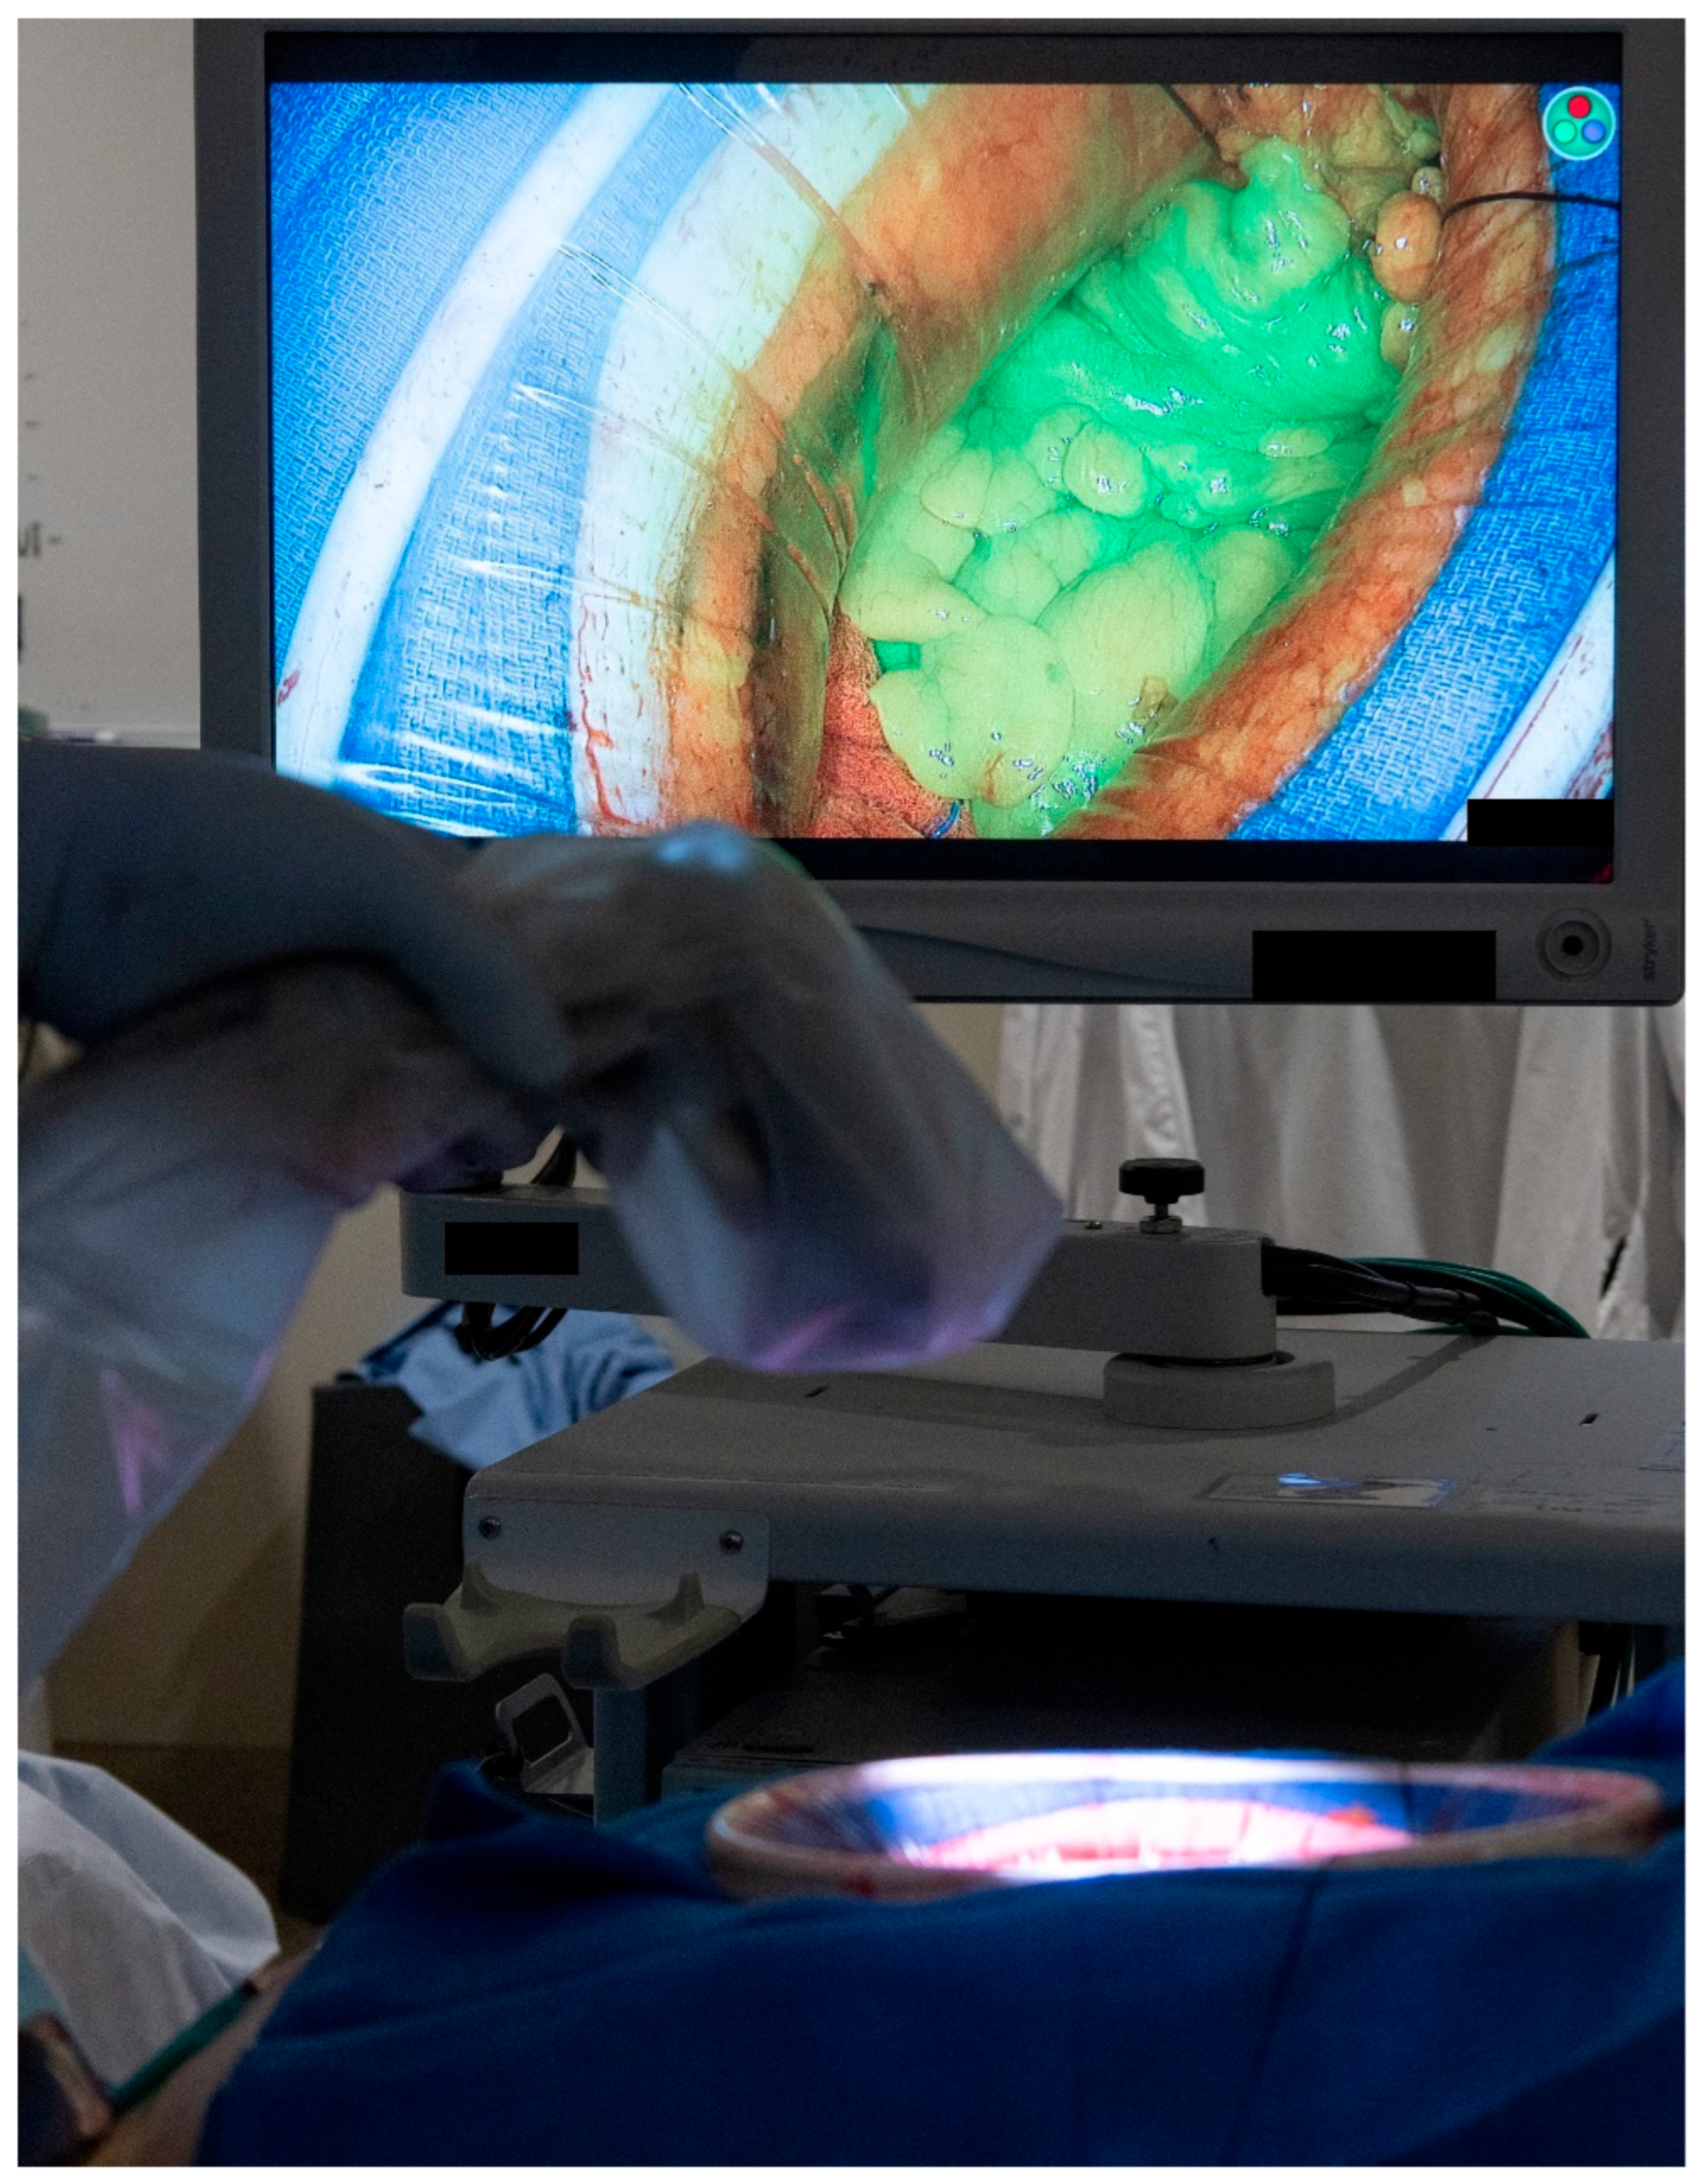

Each patient’s clinicopathological and operative characteristics are described in the Section 3, along with a technical description of each flap type and its associated outcomes. Continuous variables are expressed as medians with interquartile range (IQR). Adequate blood supply to each of the flaps was confirmed using either Doppler ultrasonography or the use of indocyanine green. The protocol in our institution is to administer 3 mL of indocyanine green followed by an immediate 5 mL flush of normal saline. The tissue of interest is then immediately assessed for adequate perfusion using Stryker’s SPY-PHI portable handheld imaging system (See Figure 1).

Figure 1.

Intra-operative assessment of tissue perfusion using the indocyanine green and the SPY-PHI portable handheld imaging system from Stryker. (Used with permission from the Mayo Foundation for Medical Education and Research; all rights reserved).